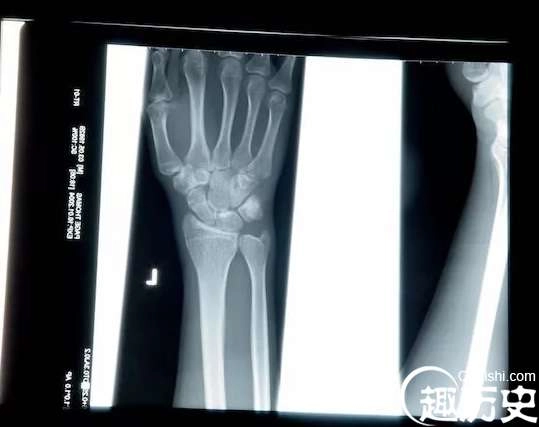

X射线

十九世纪末,一位德国物理学家在研究阴极射线时,把房间全部弄黑,还用黑色硬纸给放电管做了个封套。可是当他切断电源后,却意外发现一米以外的一个小工作台上有闪光——这是一种新的无形的射线。他在妻子的手上测试,发现光线会穿过皮肉、木头和其他物质,但不会穿过金属和骨头。因为不知道如何称呼他的意外发现,就取名为“X”(代表未知数)